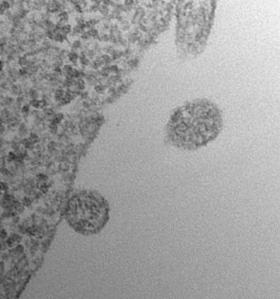

The concept of cells budding off small particles was actually first mentioned in Charles Darwin’s The Variation of Plants and Animals Under Domestication in 1868 and exosomes were first observed by electron microscopy in the 1980s. For twenty years after that, exosomes were thought by many to be nothing more than “cellular trash bags” that dump proteins deemed to have outlived their “use-by” date. This changed a few years ago, though, when a number of independent studies showed that exosomes actually contain not only protein but also RNA. This discovery opened the possibility of using the RNA in exosomes floating around in bodily fluids to learn all kinds of secrets about the cells that release them.

Exosome Micrograph

I spy a novel class of biomarkers (Image courtesy Johan Skog and Casey Maguire, Massachusetts General Hospital)